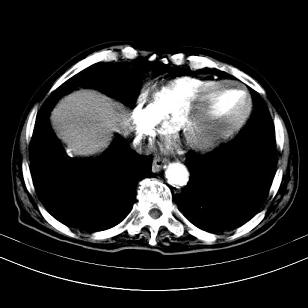

标题: CT19407:肝内还是肝外原发性肿瘤??

男,63岁,高血压病史40余年,

考虑右肝后叶肝癌伴多发肝内转移

考虑右肝后叶肝癌(部分外生)伴肝内多发性转移;右侧肾上腺区恶性肿瘤并肝转移待排。

右侧肾上腺区恶性肿瘤并肝转移

考虑右肝后叶肝癌(外生型)伴肝内转移。

考虑右侧肾上腺肿瘤并肝内多发转移。右侧肾上腺呈“八”字形,包括内侧枝及外侧枝,内侧枝受压,考虑外侧枝原发肿瘤。”

考虑肝右后叶肝癌(部分外生)伴肝内多发性转移;不排除右侧肾上腺区恶性嗜铬细胞瘤并肝转移。